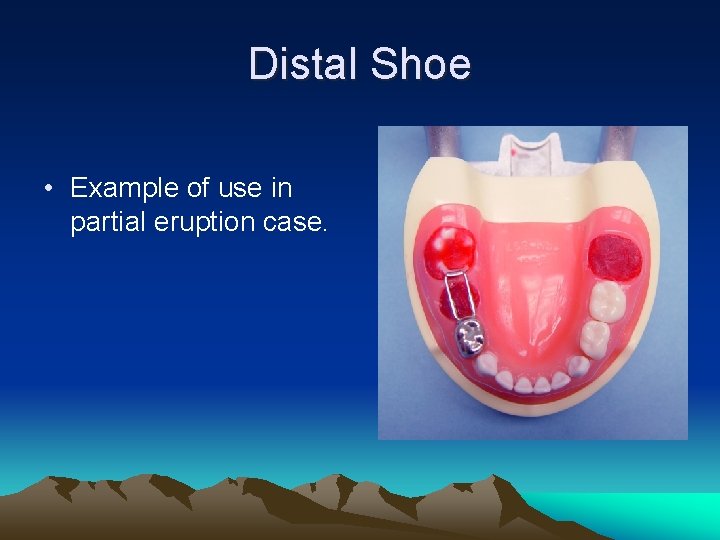

Distal Shoe • Example of use in partial eruption case.